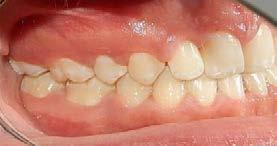

Entre los elementos que conforman al sistema estomatognático, están los dientes caninos, órganos dentales esenciales en la fisiología masticatoria; punto de unión y continuidad estética entre la línea de la sonrisa y el corredor posterior del arco dental, además de que ejercen la función de pilares estabilizadores en la oclusión fisiológica (Figura 1).

Los caninos son indispensables durante los movimientos de lateralidad y vitales para la continuidad de los arcos dentales, tanto en la dentición decidua como en la permanente; son responsables del funcionamiento y la armonía oclusal. Su posición adecuada en el arco asegura un buen contorno de la cara, sonrisa agradable y armónica con la estética facial. (Figura 2).

El canino divide su cara vestibular en 2 vertientes, una mesial que se continúa con los incisivos y otra distal que se alinea con los dientes posteriores, razón por la cual su ausencia genera alteraciones muy importantes en la oclusión y la estabilidad fisiológica del sistema estomatognático (Figura 3).

Es por lo anterior, que durante el intercambio dentario, la vigilancia periódica, a través de radiografías, análisis de modelos de estudio y una evaluación clínica, son acciones necesarias para la planeación adecuada de un tratamiento interceptivo, en caso de llegar a ser necesario, para generar los cambios y movimientos a nivel ortopédico y ortodóntico respectivamente y así evitar en lo posible una inclusión canina (Figura 7).

En la práctica clínica, al hacer la revisión, uno de los signos clínicos motivo de alerta, correspondería a la falta de movilidad de los caninos deciduos cuando ya es tiempo en el intercambio dental,(caninos superiores 10 años ±9 meses, caninos inferiores 9 años ±9 meses)9 así como señalar si existe la ausencia de los mismos, la falta de espacio en el arco dental para la erupción de los caninos

permanentes, por el que el apoyo radiográfico inicial confirmará la posibilidad de una inclusión canina en proceso (Figura 16).